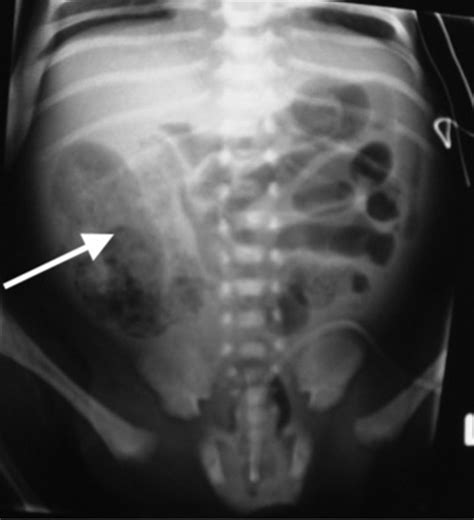

Interpreting the results of a Belly X Ray requires specialized training and expertise. Radiologists analyze the images to identify any abnormalities or signs of disease. Common findings include:

Radiologists may also use the images to assess the size and shape of organs, such as the liver, spleen, and kidneys, to detect any abnormalities.

• Kidney Stones: Hard deposits that form in the kidneys and can cause severe pain and urinary tract infections.